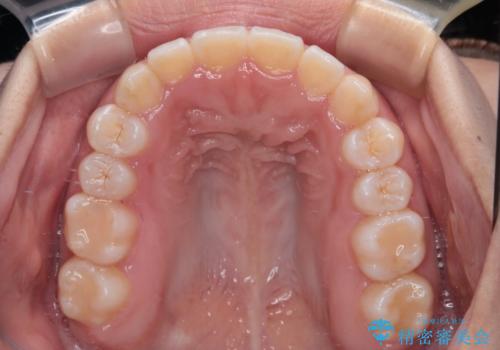

前歯のクロスバイトを改善 インビザライン・モデレートによる矯正治療

- 上下前歯のクロスバイトと叢生を気にして来院された患者様です。

インビザラインでの治療を希望されていて、デコボコの程度が中等度であり、安価なパッケージにて対応可能と判断されたため、インビザライン・モデレートを用いて矯正治療を行うこととしました。